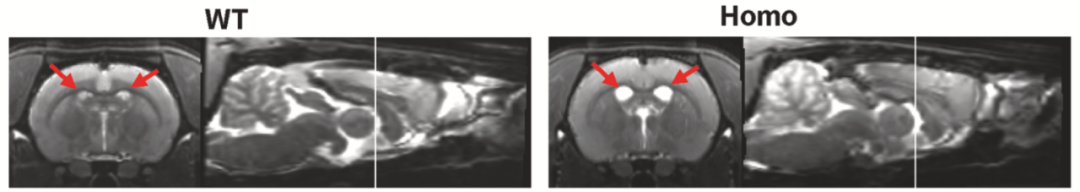

此外,这个大鼠模型还表现出由细胞凋亡和坏死性凋亡介导的神经元死亡,以及大脑皮层的严重萎缩,从MRI图像上可以观察到脑室扩大。而无论是转基因的“一代小鼠模型”[5],还是基因敲入的“二代小鼠模型”[6],都没有出现神经元的死亡或脑萎缩。

冠状面上,与 WT 相比,纯合AppNL-G-F大鼠的侧脑室扩大